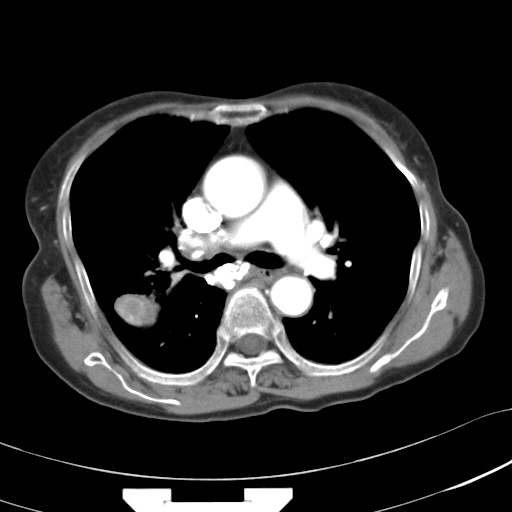

以下是引用hhcckk在2007-3-2 14:51:00的发言:[br]考虑结核球可能性大,依据[br]1病灶在下叶背段,结核的好发部位[br]2病灶内有大量的钙化,纵隔内有大量的淋巴结钙化[br]3重要的是半年前与现在相比无变化,假如是肿瘤的话不会这么‘善良’[br]4病灶周围卫星灶不明显,病灶有毛刺,胸膜凹陷,肿瘤不能完全排除,有条件的话最好做个活检